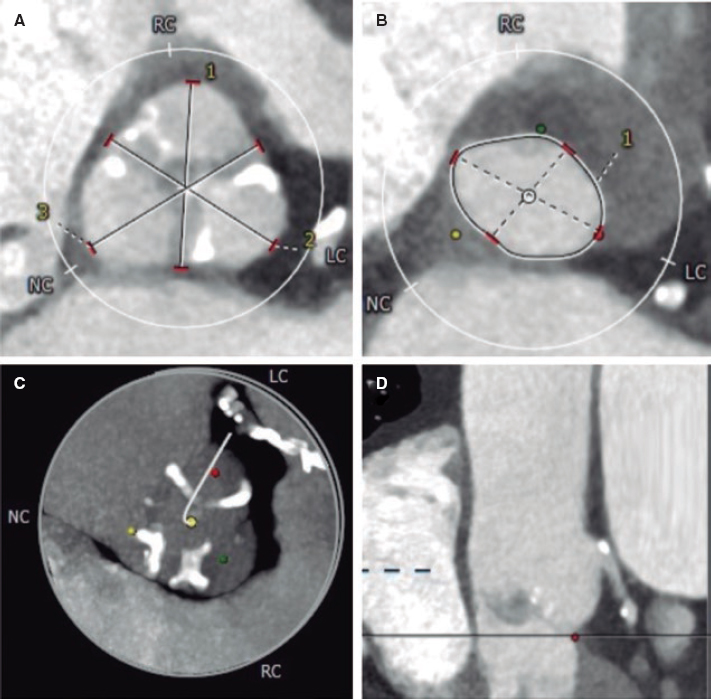

A 48-year-old woman with congenital pulmonary stenosis who required surgical valvuloplasty in 1978 presented with progressive dyspnea. The cardiovascular magnetic resonance imaging performed confirmed the presence of dilated right ventricle, severe regurgitation, and pulmonary artery aneurysm (39 × 25 mm). The heart team decided to perform a transcatheter pulmonary valve implantation. During pre-stenting with an uncovered 15-25 mm × 47-55 mm CP Stent (NuMED, United States) mounted on a 25 mm balloon of the native right ventricular outflow tract, stent embolization with spontaneous anchoring to the left pulmonary artery occurred (video 1 of the supplementary data, and figure 1A). Since the patient remained stable, a wait-and-see approach was decided to facilitate stent endothelialization. The stent (figure 1B) was used as the anchoring substrate 2 months apart of the proximal implantation for 2 longer Andrastent XXL 57 mm-stents (Andramed, Germany) on a 30 × 40 mm XL AndraBalloon to create a landing zone for the 29 mm Sapien-3 valve. The rest of the procedure was successful (figure 1C). The patient remained asymptomatic, with no perfusion defects as confirmed by the ventilation/perfusion lung scan and a mean transvalvular gradient of 7 mmHg without any residual regurgitation at the 6-month follow-up (figure 1D).

Figure 1.

In cases of aneurysmal pulmonary trunk and dilated native/non-calcified right ventricular outflow tract, the high risk of stent or valve migration may be prevented by the “planned” implantation of a first stent of smaller dimensions in a pulmonary branch. Then, sequential proximal stents may be anchored to this landing zone, which facilitates the reconstruction of pulmonary trunk with low risk of flow compromise in the jailed pulmonary branch. Further studies to assess this scenario are warranted.